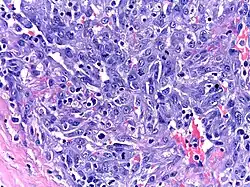

Micrograph of a Kaposi sarcoma in a lymph node biopsy of a patient with HHV8-associated MCD.

Patients with HHV-8-associated MCD are often found to have Kaposi sarcoma,[1] a cancer caused by the HHV-8 virus and most commonly seen in patients with HIV. Patients with HHV-8-associated MCD have been observed to be at greater risk of developing lymphoma.[3]